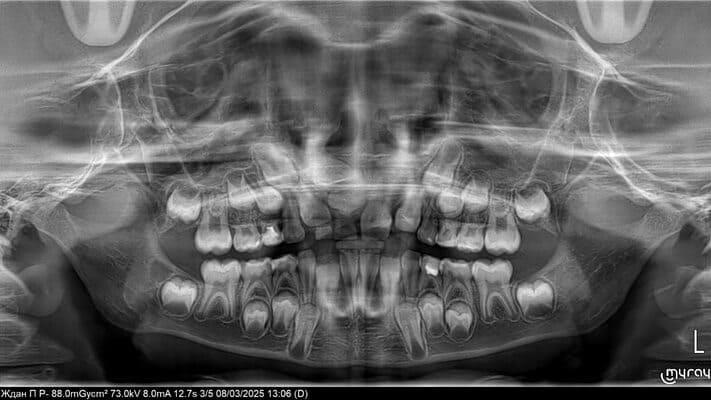

Дівчинка 7 років, перше вересня, гойдалка… Вивих постійного зуба: якщо в такій ситуації зволікати, дитина може втрати постійний зуб назавжди. Батькам порекомендували нас і пацієнти одразу приїхали. Через складність і травматичність процедур вирішено проводити лікування в анестезіологічному супроводі. Зуб поставлений на місце (репонований), проведена хірургічна обробка і ушивання рани губи. Останнє фото через рік після травми: зуб на місці і корінь продовжує розвиватись, губа повністю загоїлась